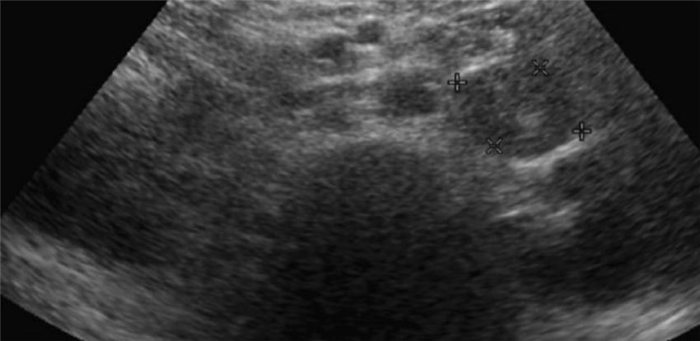

При подозрении на опухоль почки или при наличии неспецифических болей в пояснице в настоящее время широко используется ультразвуковое исследование (УЗИ) почек.

Преимуществами этого исследования является его низкая стоимость, доступность, безопасность, отсутствие вредного воздействия рентгеновских лучей. При УЗИ можно четко отличить обычную кисту почки от опухоли или подозрительного образования, требующего выполнения компьютерной томографии.

Недостатками УЗИ являются не вполне надежные результаты у тучных больных, иногда опухоль трудно выявить из-за экранирования ультразвука ребрами или газом в кишечнике. Кроме этого, результаты исследования зависят от опыта и квалификации врача, выполняющего УЗИ.